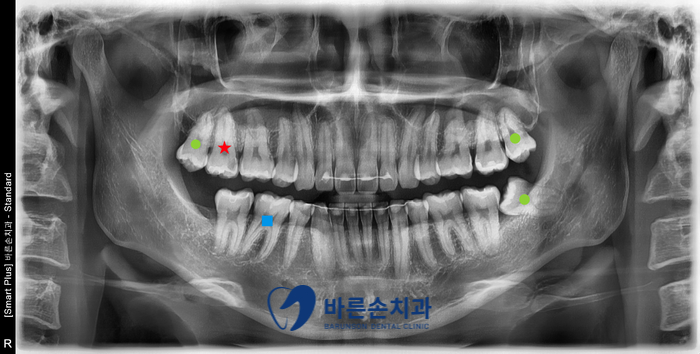

진단을 위해 엑스레이와 구강내 사진을 찍고 구강 검사를 진행하였습니다.

전체 검사 결과,

충치치료 2개와 사랑니 발치가 필요하다는 진단이 나왔습니다.

사진에서 보시면

★ 오른쪽 위 두번째 큰 어금니는 인접면 우식이 심하게 진행 -> 신경치료와 크라운

■ 오른쪽 아래 첫번째 큰 어금니의 교합면 우식 -> 인레이

● 오른쪽 위와 왼쪽 위아래 사랑니의 교합면 우식 -> 발치

치료가 필요한 상황입니다.